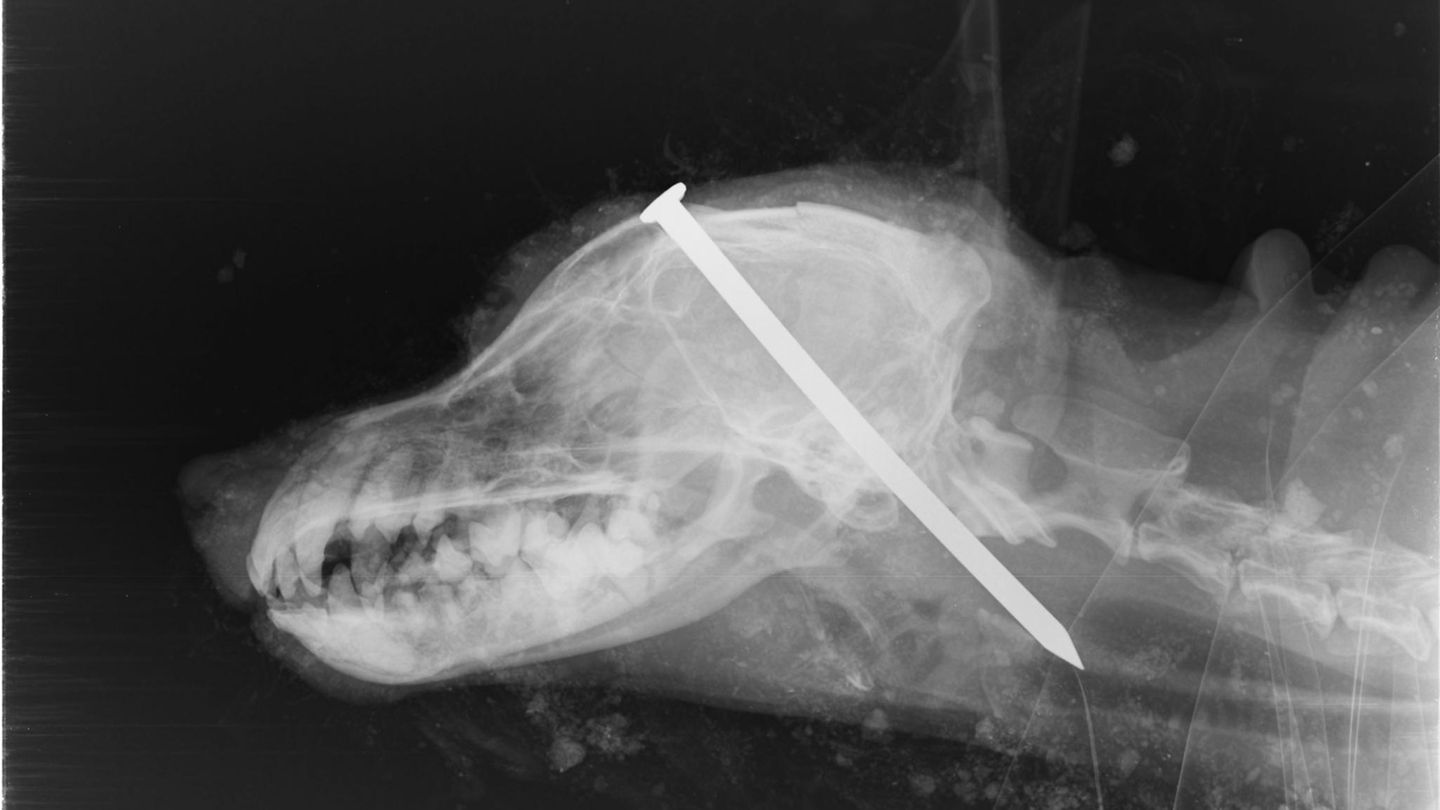

Weil sie einem Hund einen Nagel in den Kopf geschlagen und ihn lebendig begraben haben, sind zwei Männer in Großbritannien zu jeweils vier Monaten Haft verurteilt worden. Der wimmernde Terrier namens Scamp war von Spaziergängern in einem Wald entdeckt worden. Bei einem Tierarzt wurde er eingeschläfert. Auf einem Röntgenbild ist ein Nagel zu sehen, der quer im Kopf des Tieres steckt.